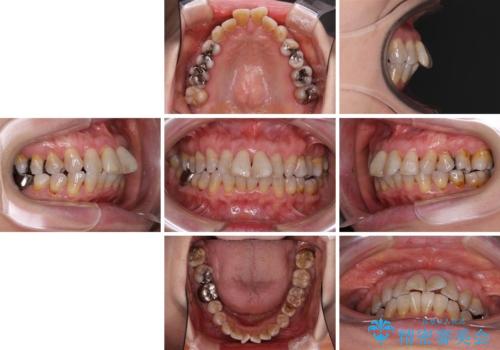

- 口元の突出感と歯の色を気にして来院された患者様です。

口元を引っ込めるために上下左右第一小臼歯4本を抜歯し、ワイヤー矯正を行うこととしました。

歯の色はホワイトニングかセラミッククラウンで対応することとしましたが、ブラックトライアングルが目立つことが予想されたため、目立つ範囲をオールセラミッククラウンで補綴することとしました。